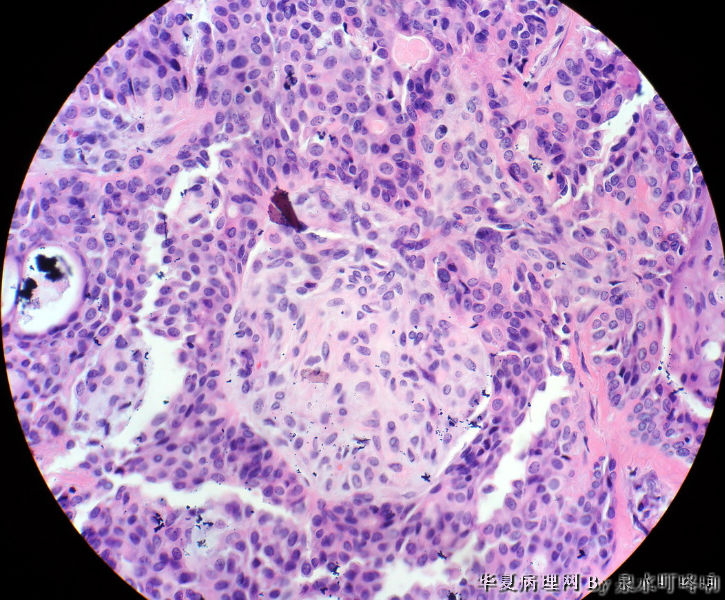

左腮腺肿物

女,38岁,左耳下方肿物,临床诊断:左腮腺肿物。

大体:灰白肿物一个,大小约4×3.5×3厘米,切面灰白,质略软,可见多发囊腔。

(左腮腺)多形性腺瘤

多形性腺瘤(粘液软骨样区域+上皮成分)

瘤组织由多种上皮成分(腺上皮+肌上皮+鳞化上皮)及黏液软骨样基质构成,多形性腺瘤可以囊性变,多结节状分布。

多形性腺瘤,肌上皮、腺上皮增生,鳞化、粘液背景

1、境界清楚

2、两种类型细胞:导管上皮+肌上皮,肌上皮与周围间质有融合现象。

3、伴有角化的鳞状分化。

4、间质:软骨粘液样间质+弹力纤维。

综上:多形性腺瘤。